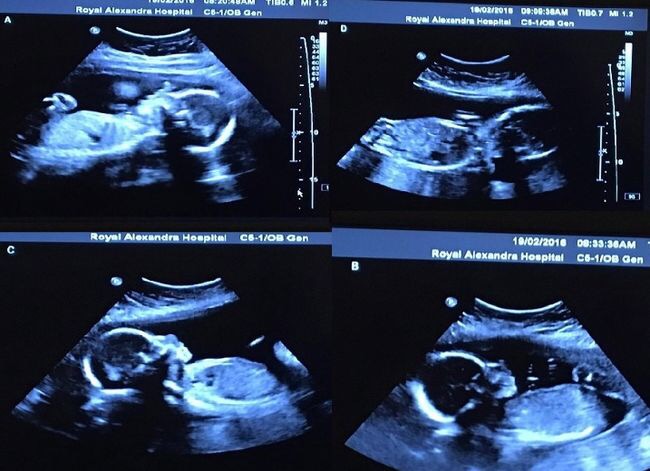

Pas getrouwd en zwanger van hun eerste kindje. Bethani en Tim Webb uit Canada zijn as happy as can be. Hopend op een goede check-up neemt Bethani plaats in de stoel bij de echoscopiste.

Een goede check-up is het zeker. Maar niet alleen van 1 gezond meisje; ook haar 3 (!) identieke zusjes bewegen vrolijk rond in mama’s buik!

Bethani is nu 29 weken zwanger en verblijft in het ziekenhuis zodat ze haar goed in de gaten kunnen houden. De doktoren hopen dat de 4 meisjes tot in ieder geval 32 weken veilig in mama’s buik blijven en eind april/begin mei geboren zullen worden.